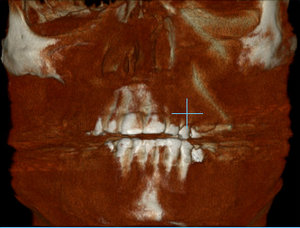

Под новый год заболела челюсть у виска справа (подозреваю, что на фоне проходящего гриппа). Сделал КТ челюсти. Специалистов у нас нет, предложили ехать за консультацией в краевой центр. Можно по снимку определить, что это у меня случилось?

Комментарий №175658 Комментарий №175658 Комментарий №175658 Комментарий №175658

• Описанная проблема может быть связана с височно-нижнечелюстным суставом. Возникнуть симптом может при дегенеративном поражении височно-нижнечелюстного сустава или вследствие других проблем в челюстно-лицевой области (патология прикуса, бруксизм, мышечный гипертонус). Рекомендуем Вам обратиться на консультацию к гнатологу или специалисту в области нейромышечной стоматологии